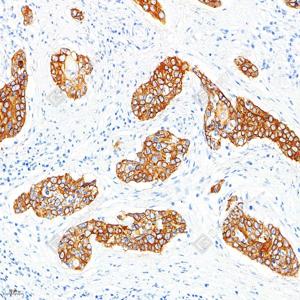

IHC检测Cytokeratin 1蛋白(货号 GB151018). 样品: 人宫颈癌, 4%多聚甲醛 (货号G1101) 固定12-24小时. 抗原修复: 柠檬酸抗原修复液(干粉, pH 6.0) (G1201), 高压锅均匀喷气计时2分钟. —抗: 1: 1000稀释, 4℃ 孵育过夜. 二抗: S-vision免疫组化多聚二抗(山羊抗兔),即用型 (货号G1302), 室温孵育20分钟. |

|